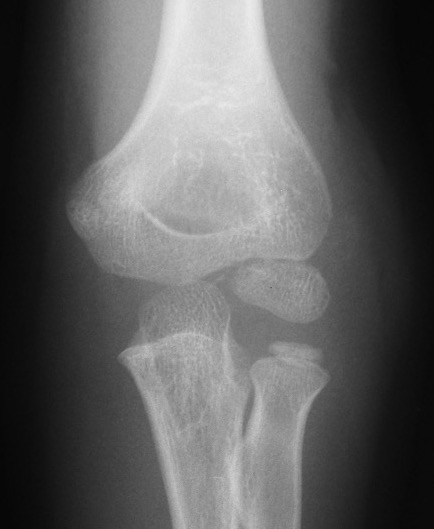

Injured left elbow v injury right elbow

Open reduction of displaced lateral condyle in left elbow